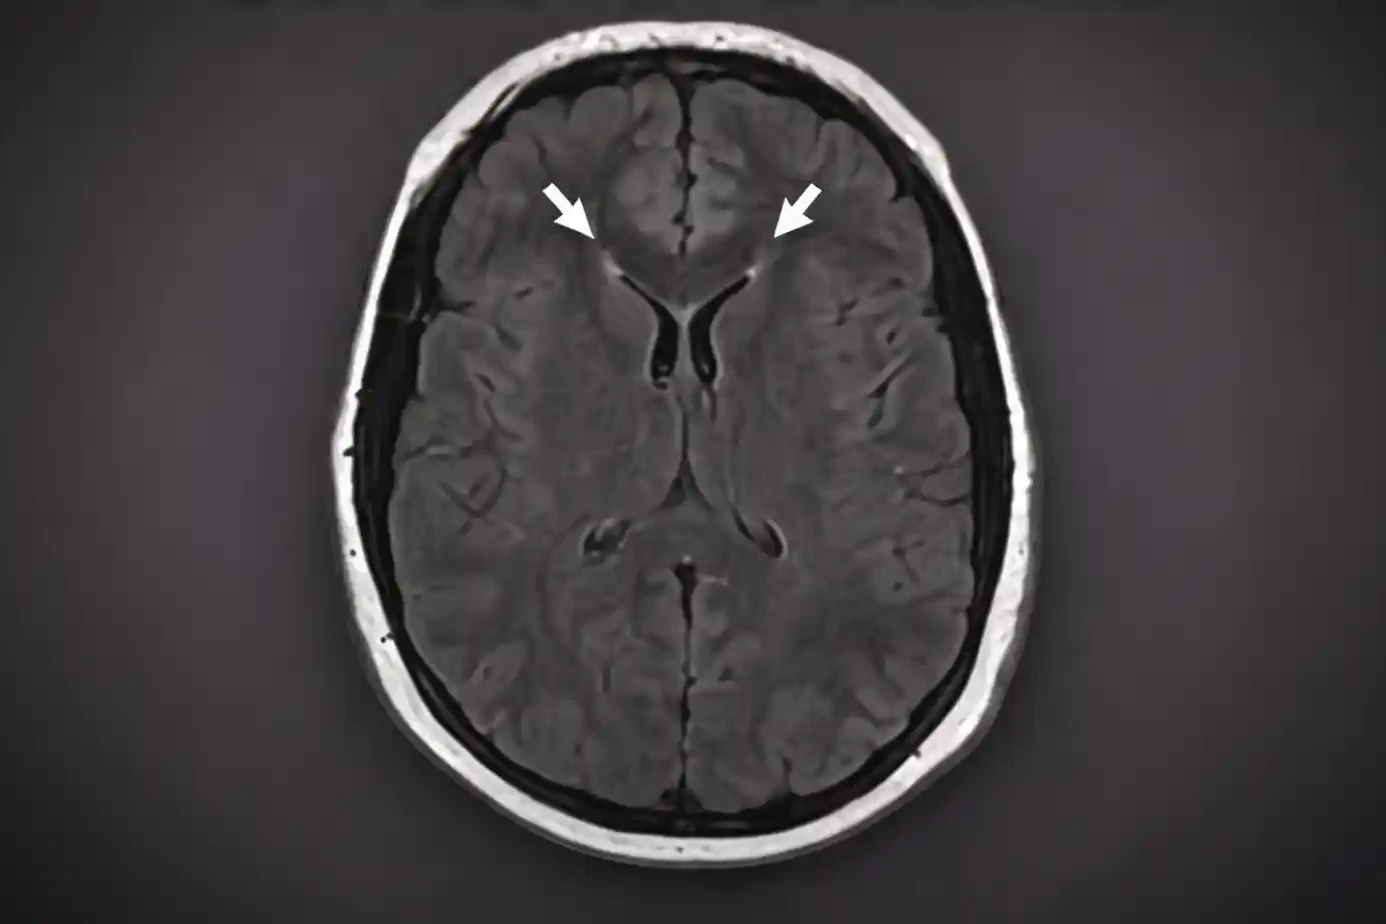

Cerebral Edema: Causes, Types, Symptoms & Treatment Explained

Edema means fluid builds up in a part of the body where it should not be. When this buildup happens…